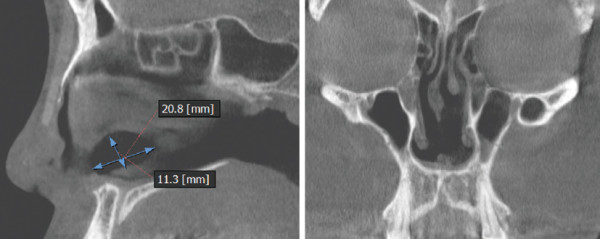

그림 1. 비중격 중간 부위에 2㎝×1.1㎝가량의 원형 천공이 관찰되었다.

1982년생 여성 환자로 세 번의 코 성형 후 콧등 파임, 코

막힘 등을 주소로 내원하였다. 수술 전 검사상 비중격

중간 부위에 20㎜×11㎜가량의 원형 천공이 관찰되었다